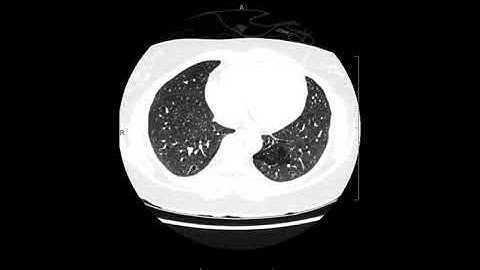

pulmonary sequestration